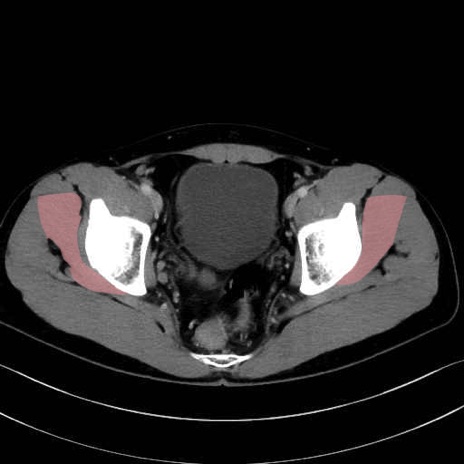

小殿筋 (Gluteus minimus)